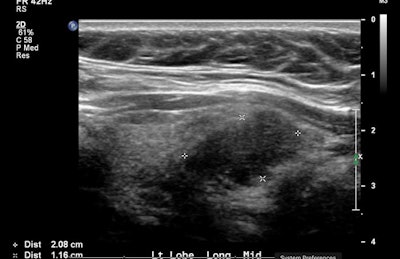

Echogenicity refers to a nodule's reflectivity relative to adjacent thyroid tissue and cervical strap musculature. Traditional qualitative assessment of nodule echogenicity has been performed to observe whether a nodule is hyperechoic, isoechoic, or hypoechoic compared with the surrounding thyroid tissue or, in the case of hypoechoic nodules, the adjacent strap muscles, Nuffer said.

As part of a larger radiomics project using deep learning to predict thyroid nodule malignancy, the researchers sought to quantify the relationship between solid thyroid nodule sonographic echogenicity and malignancy. They performed a retrospective study involving 69 patients with 35 biopsy-proven malignant solid thyroid nodules and 34 biopsy-proven solid thyroid nodules.

After all nodules were segmented in longitudinal and sagittal planes, the researchers used Adobe Photoshop to calculate the mean intensity of each nodule on the best image of both planes and then averaged the results to arrive at the final mean intensity value. Similarly, they also obtained the mean intensity value of a sample of background thyroid parenchyma adjacent to each nodule in both planes and averaged the results to obtain the mean intensity value. A ratio was then calculated between the nodule intensity and adjacent thyroid parenchyma intensity.